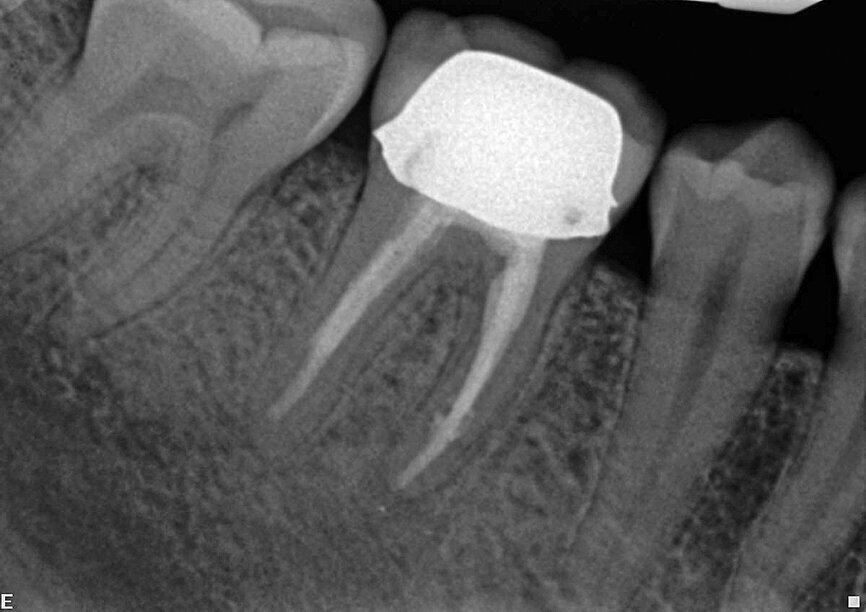

Fig. 3: A necrotic/infected case: Lower premolar of the patient complaining of dull and pulsating pain. The infection was not limited to the apical part, but was also located in the lateral mid-root section. Postoperative X-ray shows a 3-D sealing of the apical area with its anastomosis and of the lateral and accessory canals in mid root.